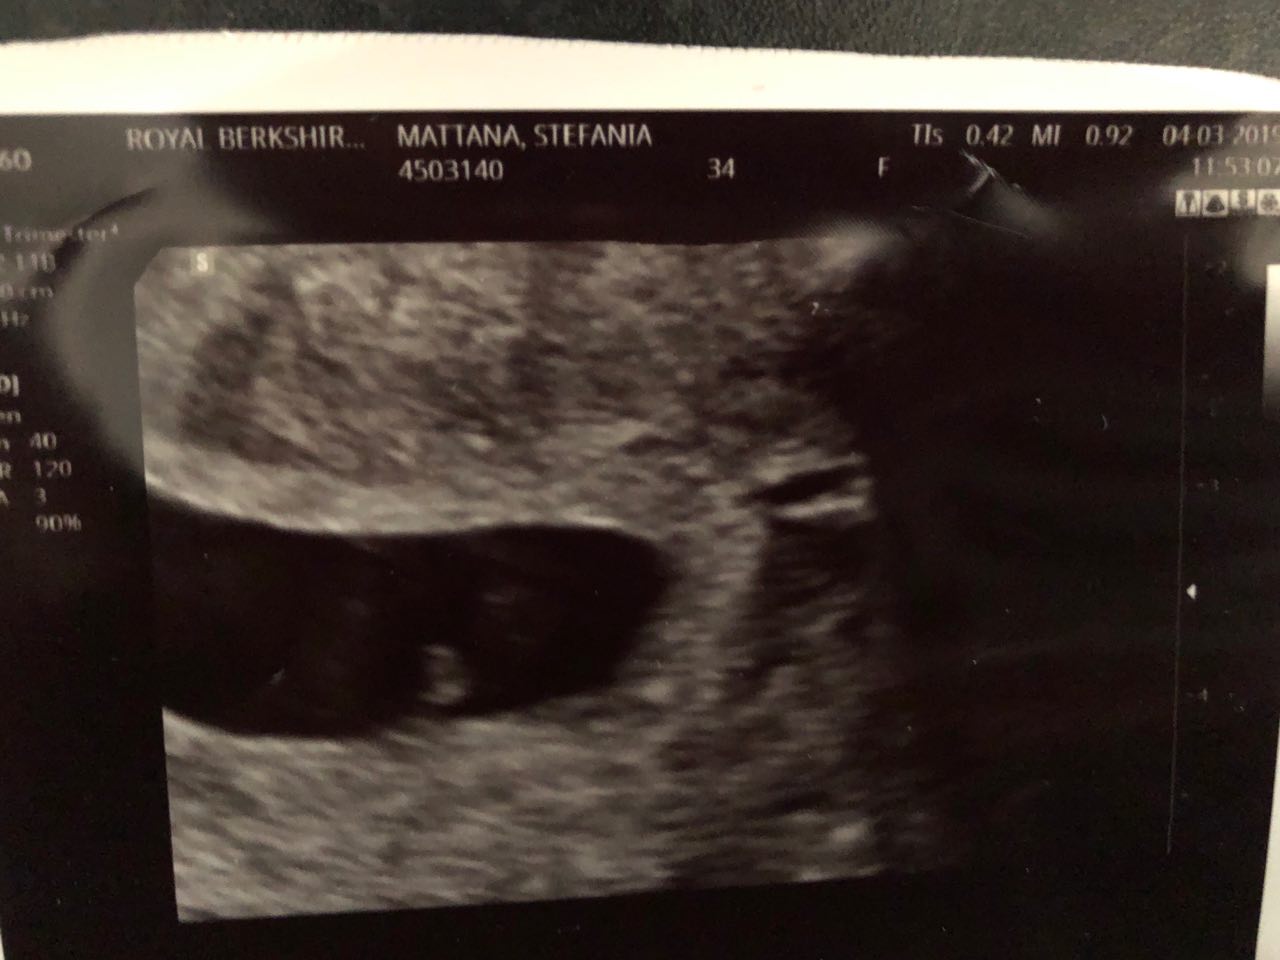

Meet Frosty’s heart

Here it is, Frosty, all wrapped up in their oven, chilling, like nothing happened. From the scan in real time we could see their heart beating, like an intermitting tiny white-ish thing flashing within Frosty’s body.

If you have no idea what you’re looking at, here’s some indications (please note that cuore means heart in Italian.

Frosty is now the size of a blueberry, or a bee, if you will, measuring around 1.3 cm and weighing around 0.5gr.